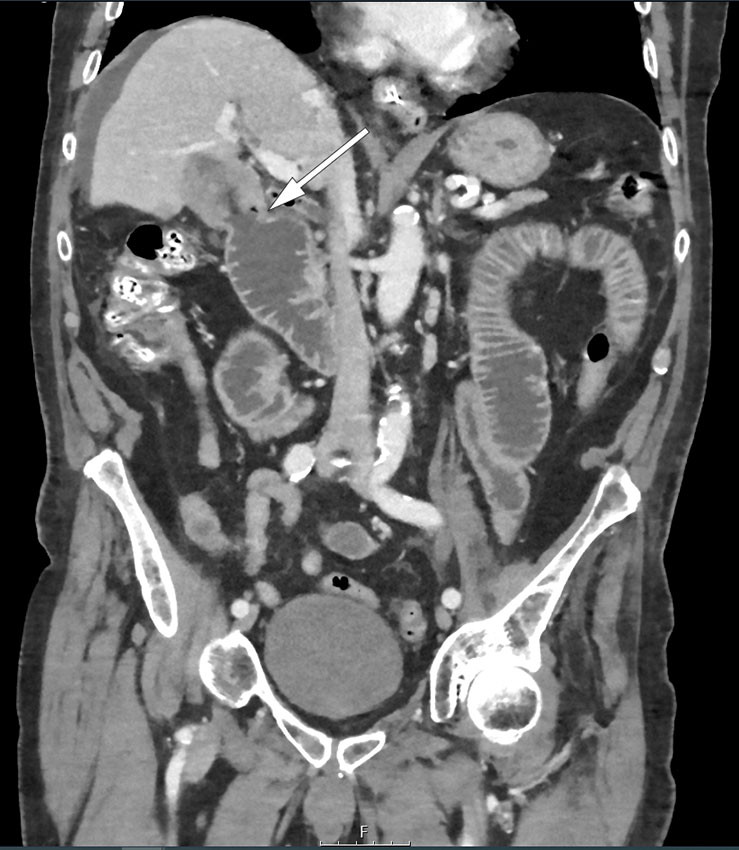

Our patient had a non-radiopaque concretion that was barely visualised on CT. Ultrasound revealed a clear concretion that cast a shadow, and based on the ultrasound findings the outline of this could just be made out on plain abdominal film. A repeat CT scan also revealed air in the biliary tree and cholecystoduodenal fistula (Figure 2). A large concretion in the gallbladder could be discerned on CT images from four years previously, but no fistula or tumour.